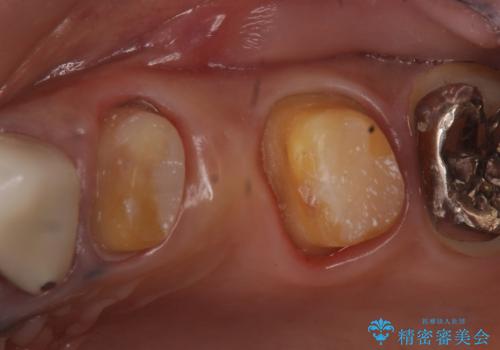

- 昔治療した左上56の延長ブリッジをきちんと治療しなおしたいといらっしゃった方の症例です。

古いブリッジを除去後、オールセラミッククラウンによる補綴を行いました。

- オールセラミッククラウン…¥100,000×3、仮歯…¥10,000×3費用は治療当時の料金となります